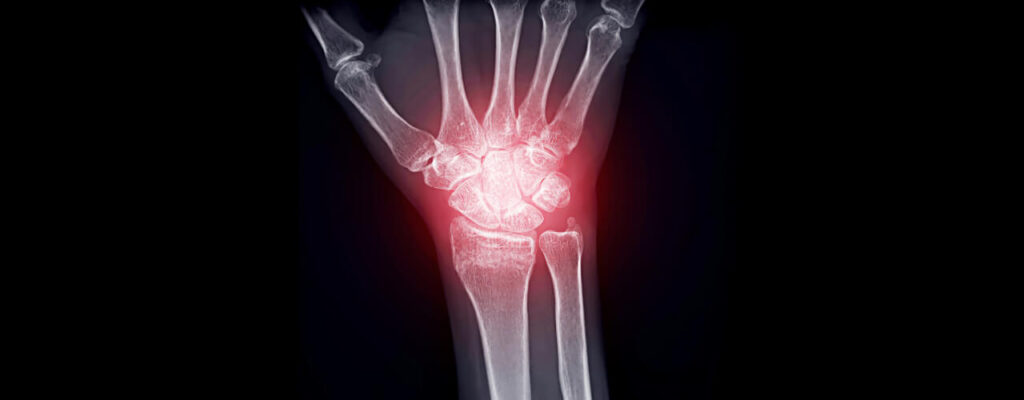

How to Manage Joint Inflammation from Arthritis